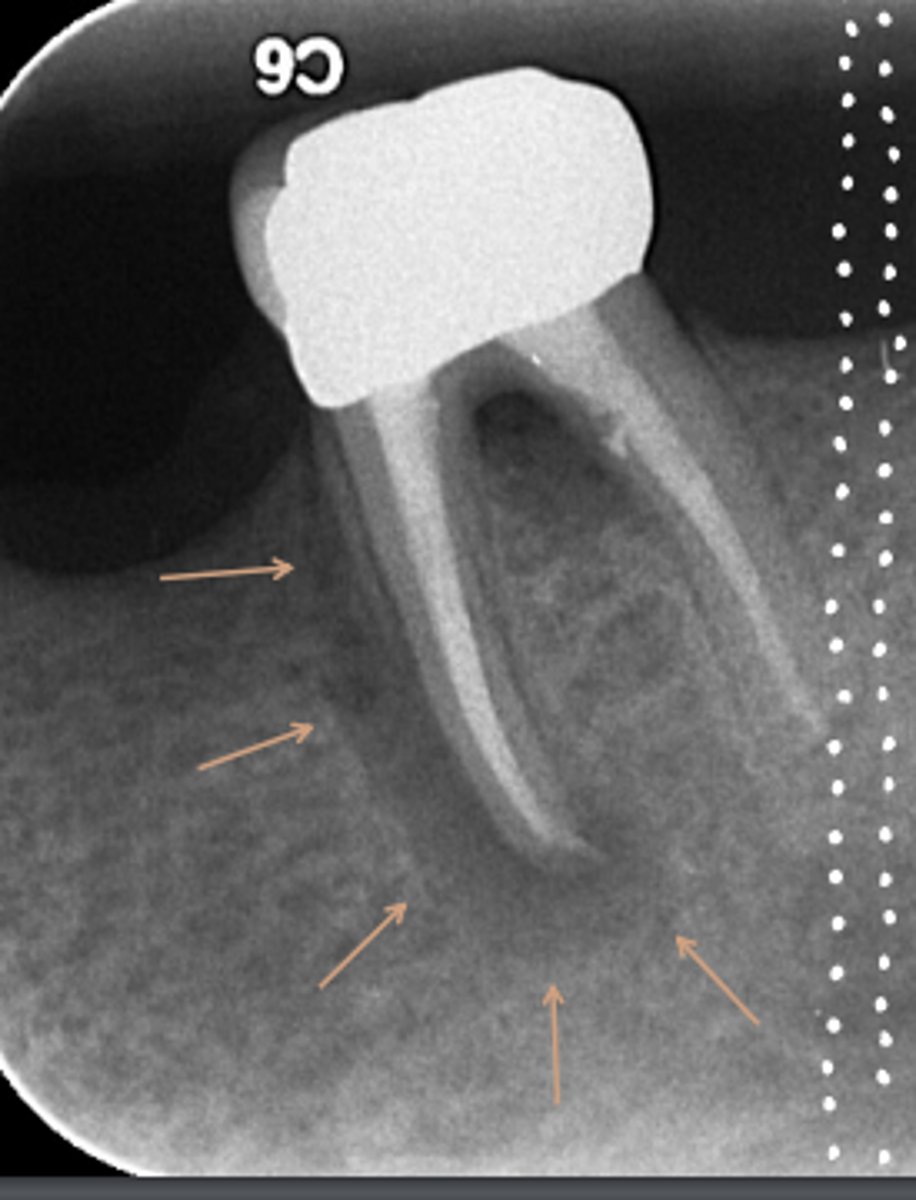

What are the radiographic findings on #19?

- Crown

- Post D Canal

- PARL Mesial and Distal Root

- PARL in Mesial and Distal Root

- Discontinuation of LD